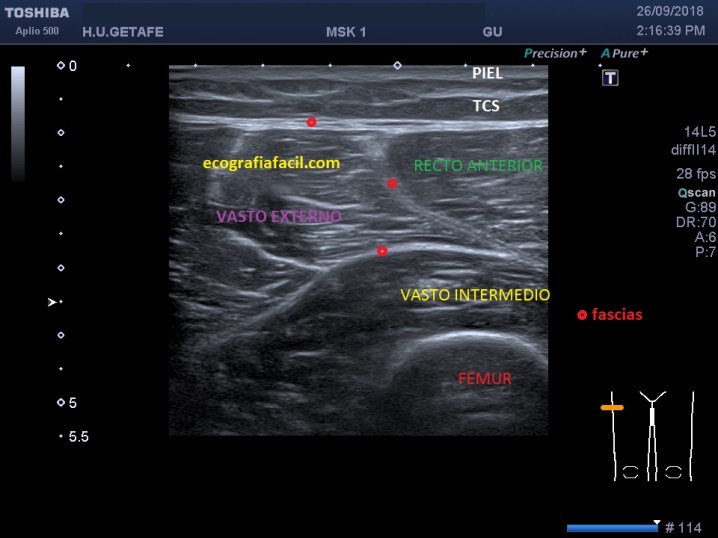

En esa misma localización y el corte Transverso observamos lo mismo, el músculo recto anterior ausente en su localización normal y se observa un área hipoecogénica que puede corresponder al hematoma…así:

We placed the probe in Longitudinal in the long axis of the thigh and we observed a retracted anterior rectum that does not insert in the patella in a normal way and that does not run parallel to the long axis of the femur. The retraction occurs when the tendon fibers corresponding to the rectum disengage from the patella, the quadriceps tendon is for you to understand, the union in a single tendon of the 4 quadriceps muscles that finally insert the proximal side of the sesamoid bone par excellence , the kneecap. In that same location and the Transverse section we observed the same thing, the anterior rectus muscle absent in its normal location and a hypoechoic area that can correspond to the hematoma is observed … like this:

Corte Transverso

Entre las líneas azules debería estar el Recto Anterior, está ausente, sustituido por grasa y vemos la presencia un a estructura alargada hipoecogénica correspondiente a un hematoma que apoya sobre el vasto intermedio.

Finalmente tenemos dos imágenes comparativas de los dos Muslos, el patológico y el normal contralateral, eso sí, debe ser comparativo el estudio en la misma zona exactamente de los dos muslos para que la fiabilidad de la imagen sea lo más alta posible.